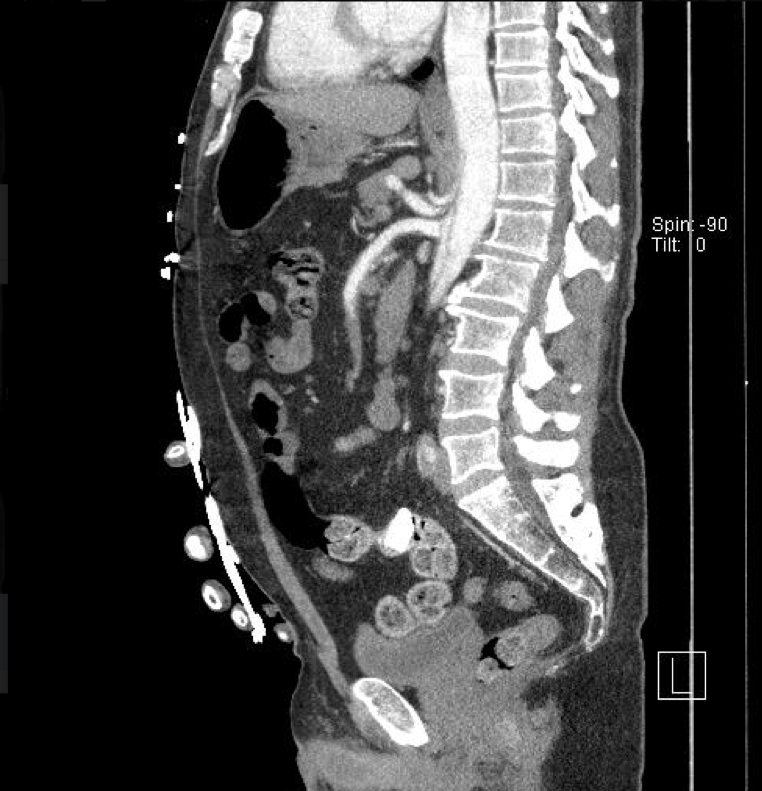

At initial evaluation, patient appeared to not have pulses on his left leg including dorsalis pedis, posterior tibialis, popliteal artery and femoral artery. Seconds following the initial evaluation, patient began to state he was having chest pain. CT of chest/abdomen/pelvis with run off was ordered, and the results immediately evident:

50-65% of intimal tears originate in the ascending aorta, with 20-30% of tears originating near the left subclavian with extension to thoracic and abdominal aorta. Extension proximally and distal from initial tear will lead to clinical complications such as aortic regurgitation, cardiac tamponade, coronary/cerebral ischemia, and in our case a kidney infarction as seen by image 1.

Following our CT of the chest/abdomen/pelvis, it became apparent that our patient’s aorta had dissected through the ICA, subclavian, SMA, to the left Iliac artery, including an infarction of the left kidney. Initial medication included Labetalol, esmolol, nicardipine with propofol also aiding in blood pressure management following intubation due to airway compromise. The patient underwent emergent surgery and survived.